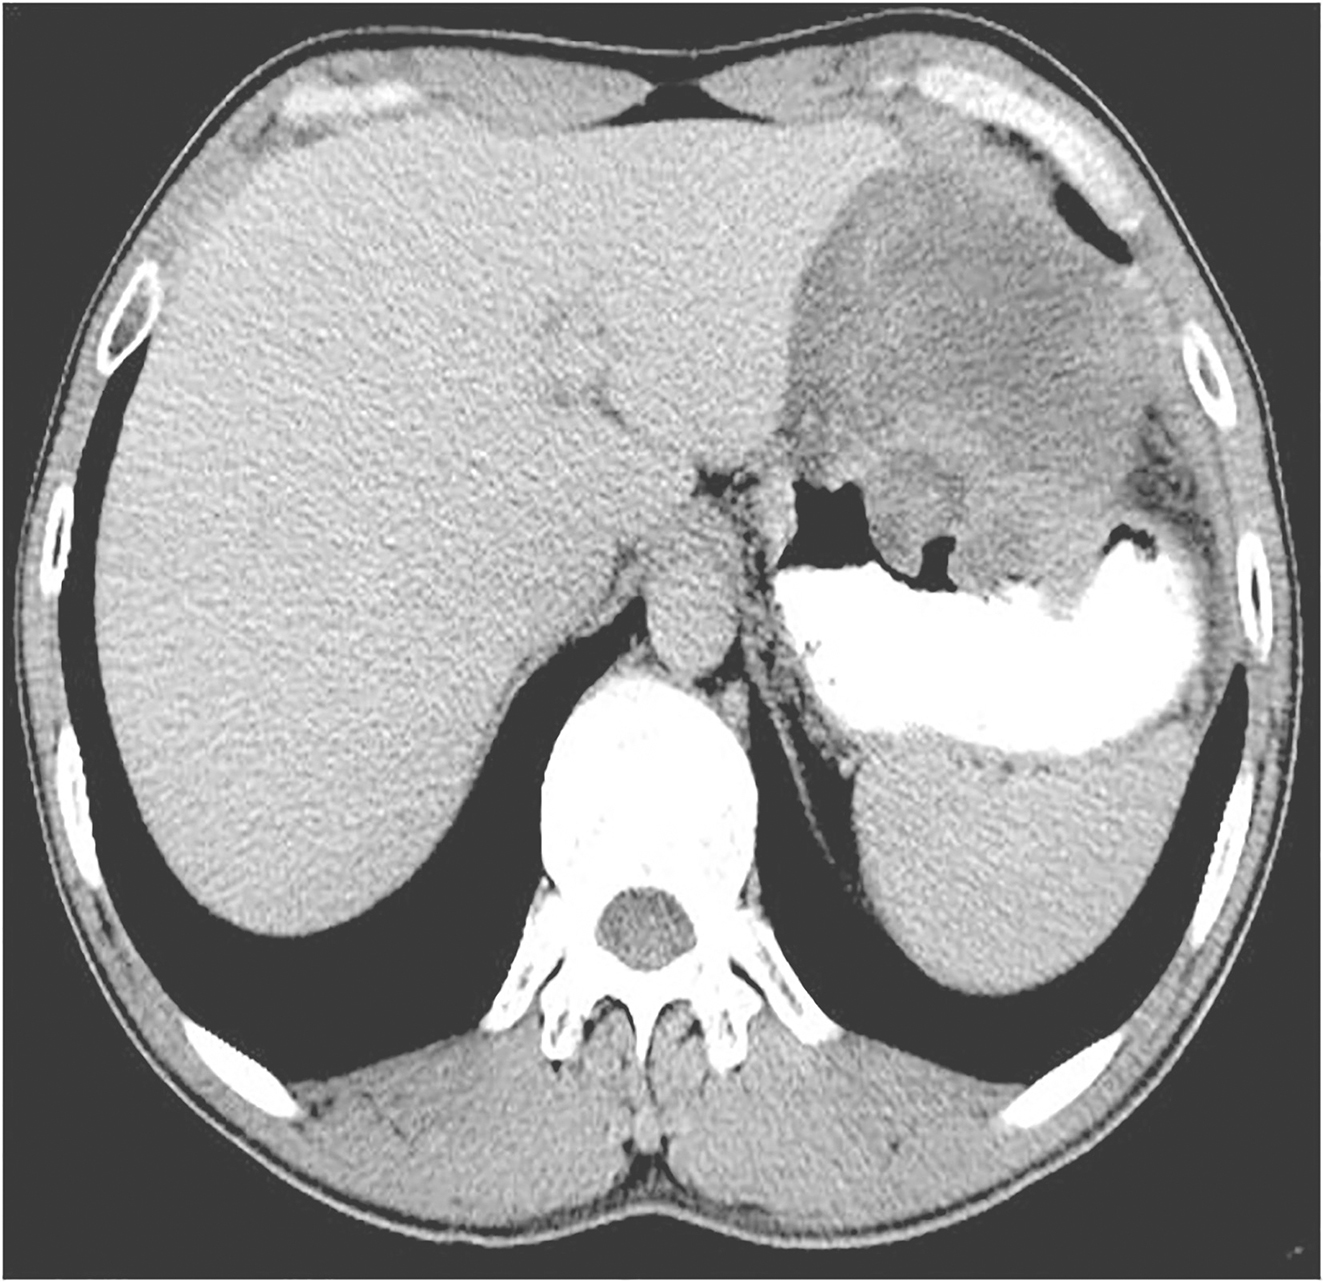

于2012年10月13日开始口服伊马替尼400mg/d 治疗。治疗3个月后CT评估肿瘤大小为120mm×87mm,治疗6个月后CT评估肿瘤大小为92mm×65mm。治疗8个月后CT示:胃底大弯侧GIST,伊马替尼治疗后,肿瘤明显退缩,大小为89mm×63mm,病灶与左侧膈肌接触面缩小,分界较前清晰(图3)。此间规律口服伊马替尼,主要不良反应为1~2度食欲减退、乏力、手足综合征,未予特殊处理,自行缓解。

图3术前治疗8个月后全腹增强CT